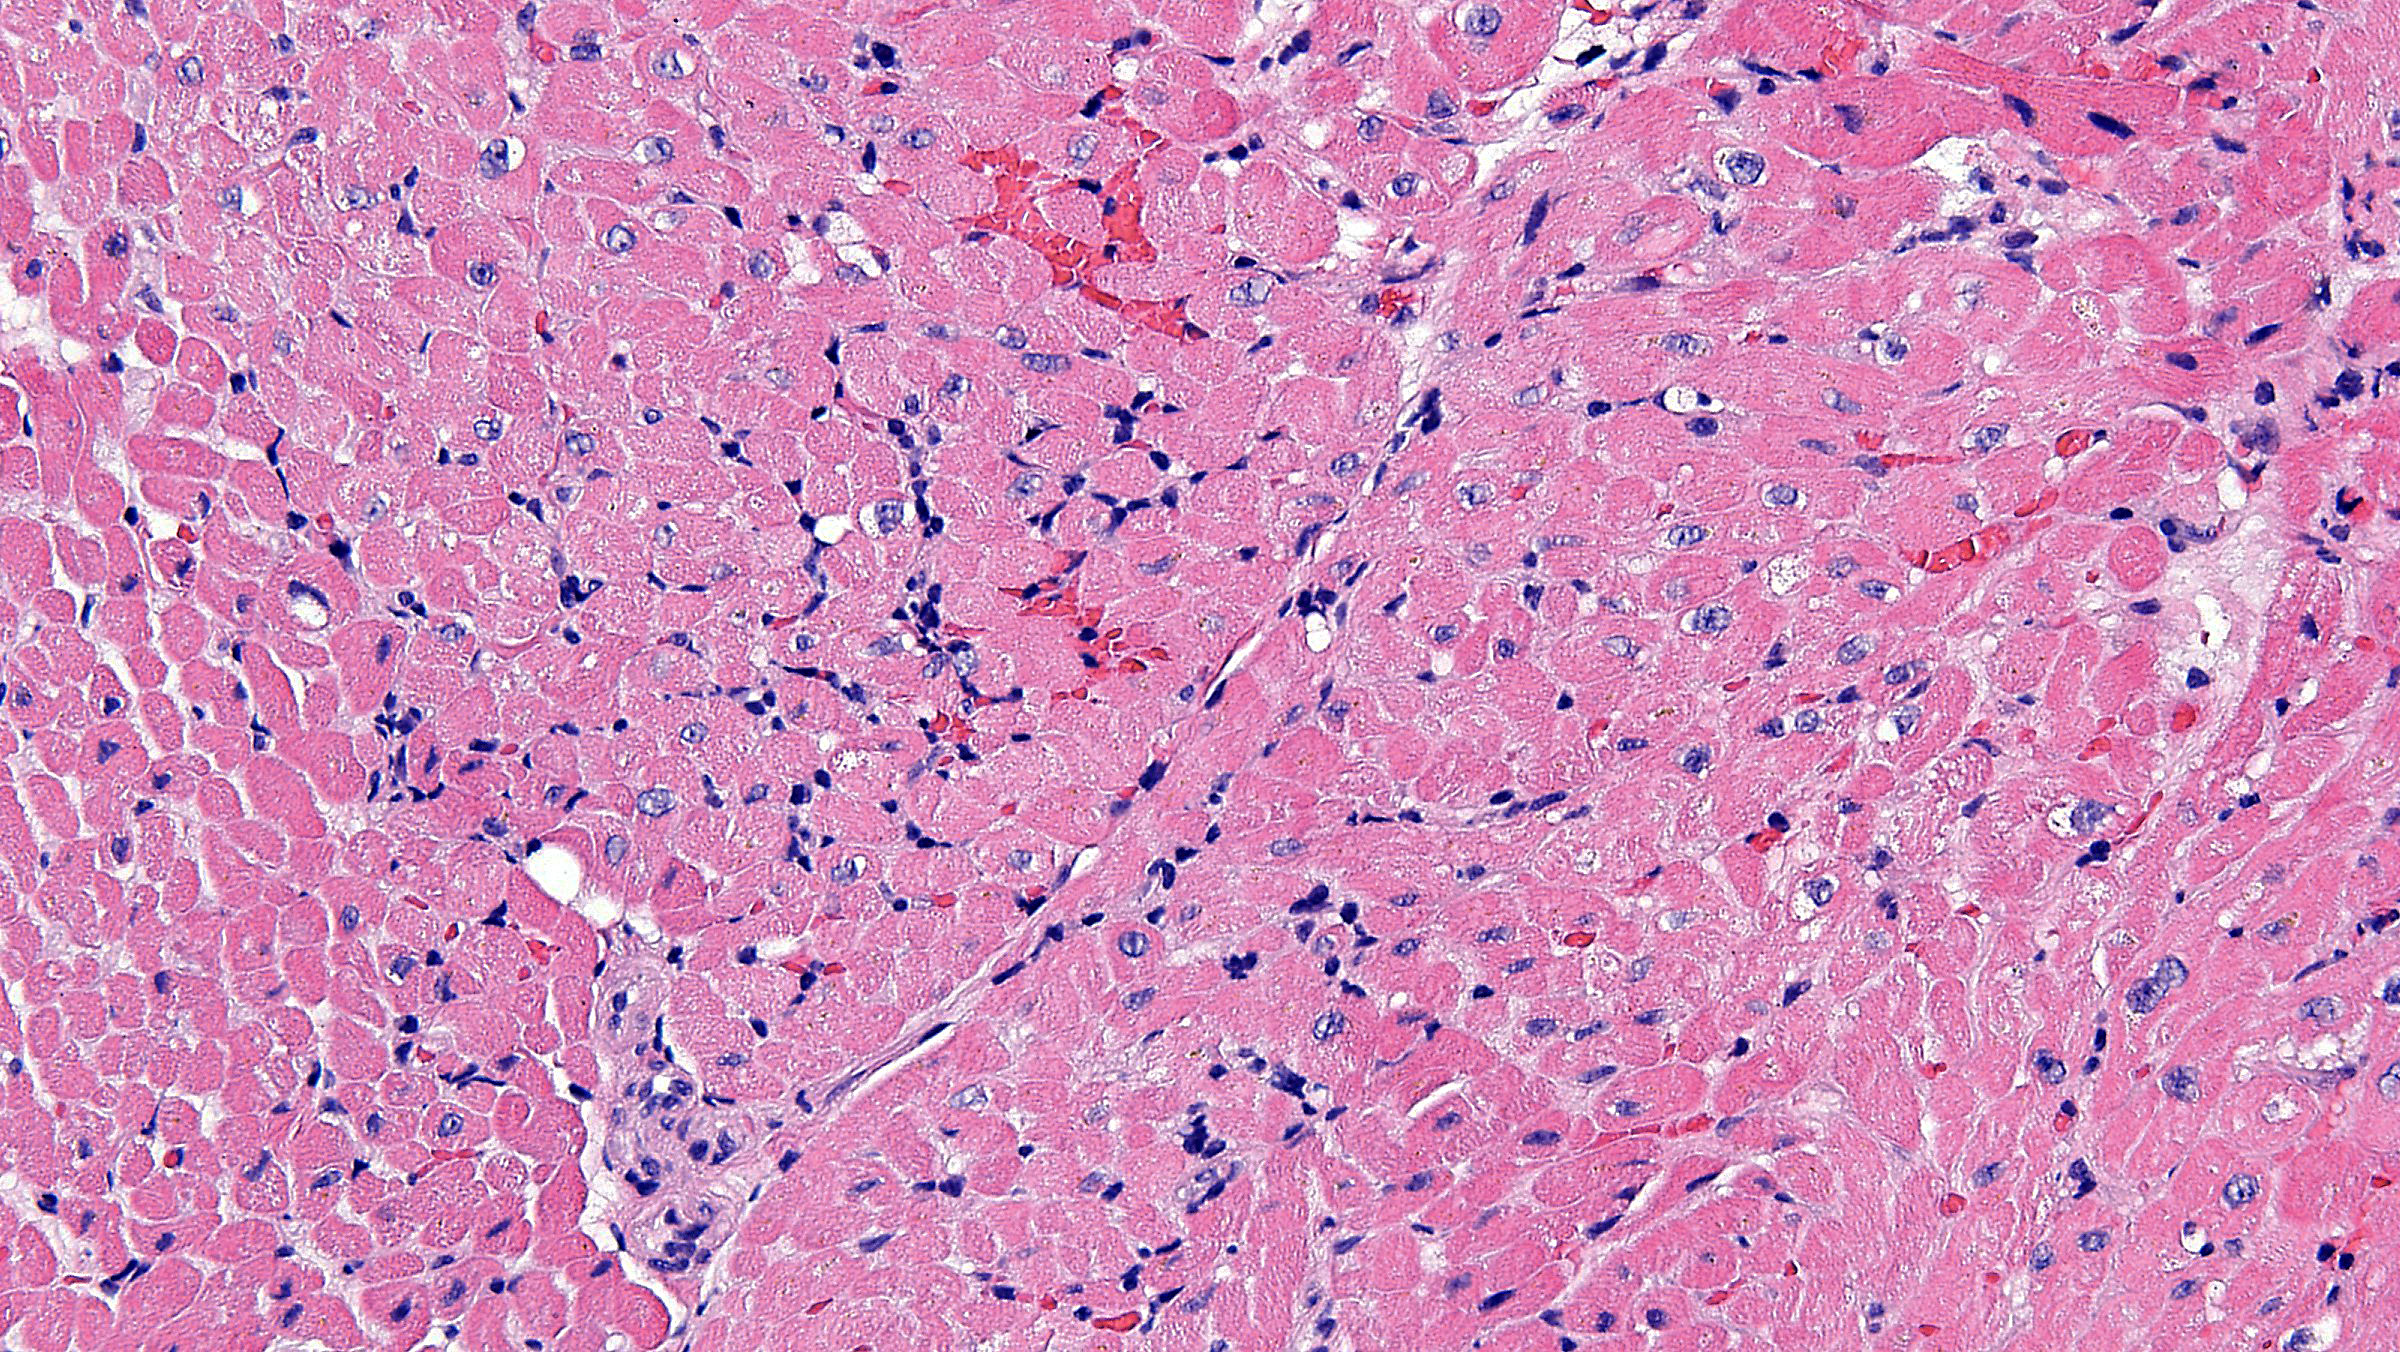

Figure A. H&E x20

Histology: The sections show myocardial tissue with a diffuse, mild to moderate increase of intravascular mononuclear cells, which are confirmed by special immunostaining for CD68 showing ~50% of focal intravascular macrophages (score 1)(figure D). Special immunostaining for C4d shows moderate staining (2+) of the endothelial cell lining of capillary vessels (Figure B, C)